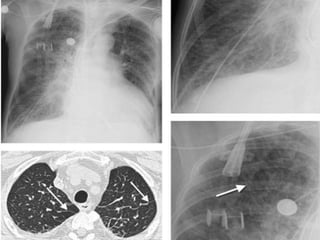

Lymphangioleiomyomatosis

(LAM).

A: PA chest radiograph shows a

right basilar pneumothorax and

two right pleural drainage

catheters. The lung volumes are

increased, which is

characteristic of LAM, and there

is diffuse reticular ILD.

B: CT scan shows bilateral thinwalled cysts and a loculated

right pneumothorax (P).